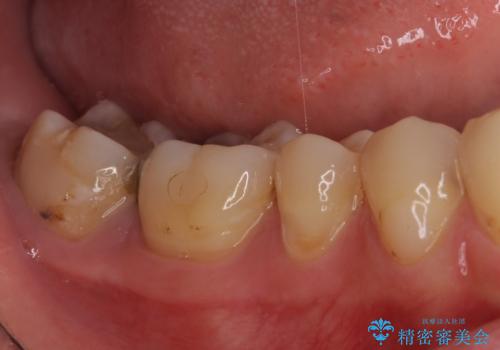

上顎の奥歯は最近銀歯による治療を行ったとのことでしたが、適合が不十分であり隙間からしみていたため、適合の良いゴールドインレーにて修復治療を行うこととしました。

下顎のむし歯は歯肉の中にまで及んでいたため、一部歯槽骨を削除し、歯肉縁上に健全歯質が位置するよう外科処置を併用しました。